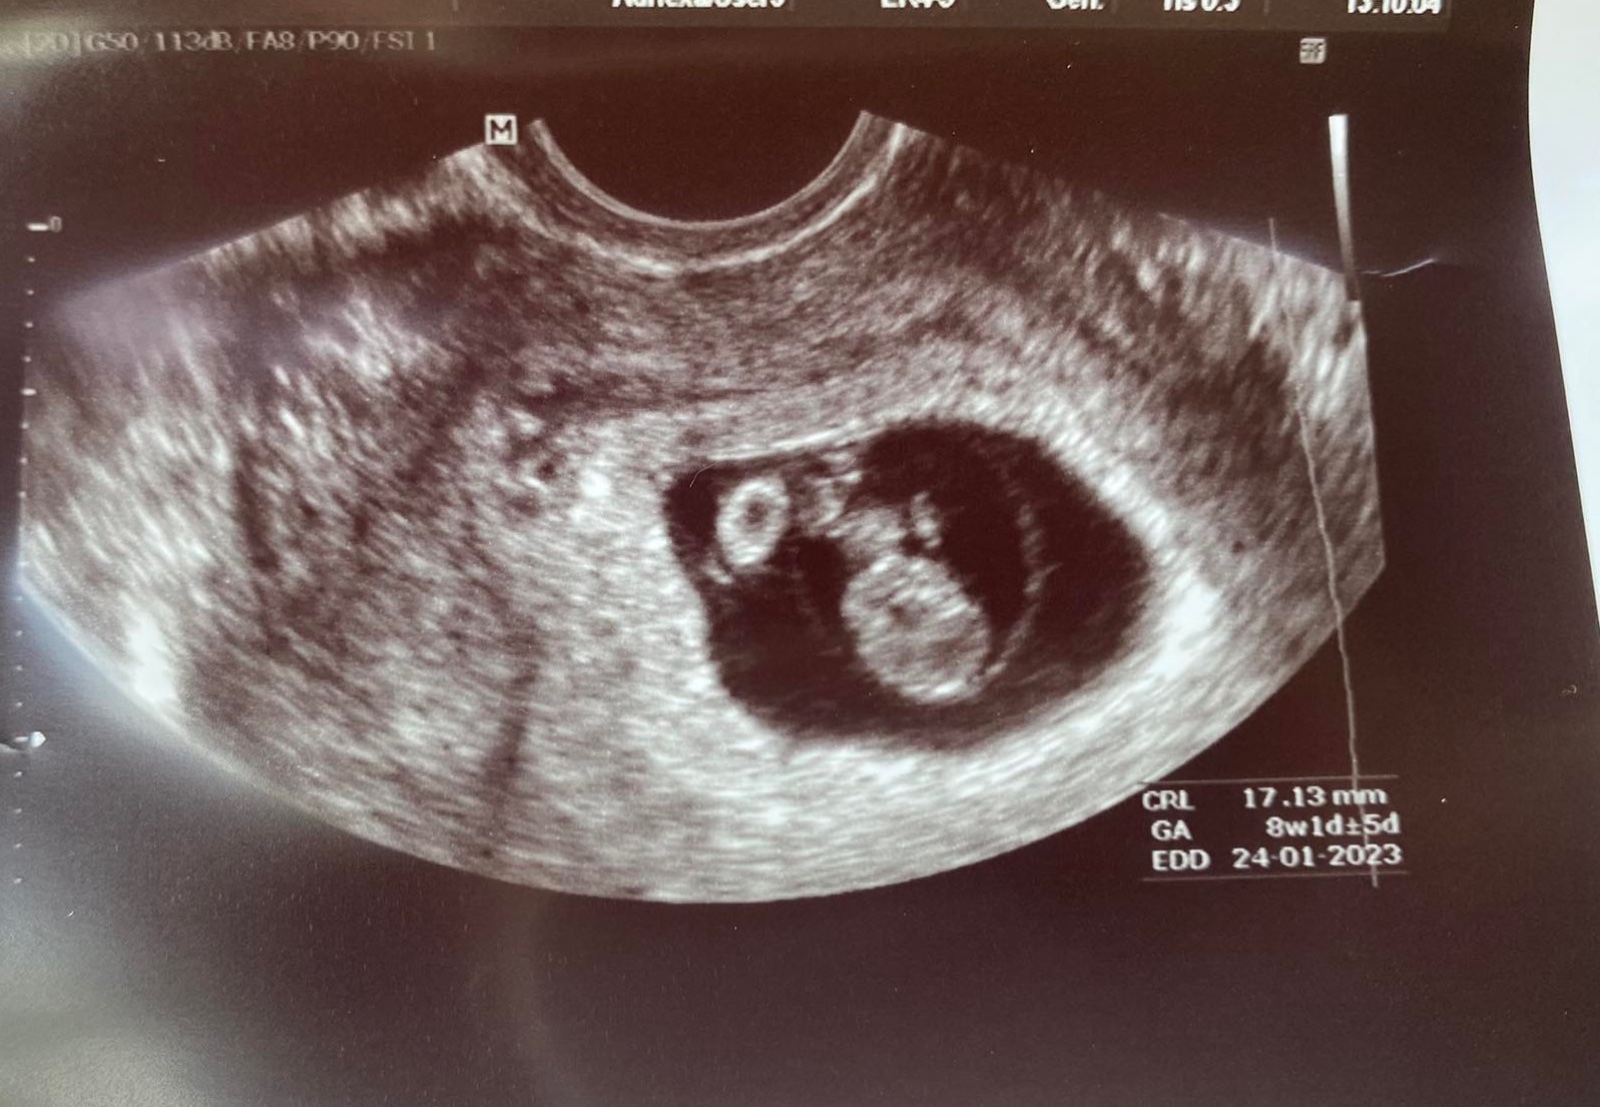

Kindervajka ako sa mate? Ja som dnes mala prvu poradnu 8+4tt dostala som tehu knizku a mam sa uz hlasit do rizikovej poradne v nemocnici kde budem rodit. Na odporucanie diabetologicky. Tak uvidime ci ma tam vezmu tam skoro. Inak mame 1.11.cm a podla sono sme.pozadu 7+1tt ale nakolko ms nemam pravidelnu a ani tie merania nie su presne nemame to riesit...

@esmee3 a my mame 7,5cm 💓

@esmee3 moj zas tuzil bo dievcatku🥹❤️ a termin z 30.12 na 24.12 tak uvidime ci tak bude ja by som chcela 20.12 kedze ja mam narodky 20.1 a 20 je moje stastne a symbolicke cislo kedze 20.9.18 sme sa dali uz s terajsim manzelom dokopy a 20.6.20 sme mali svadbu 🫶🏻a podla vypoctov sme asi aj pocali 20 marca :D tak to by bolo silne

@esmee3 jeeeeemineeeeeeeee krasne tiez 🫶🏻🫶🏻🫶🏻uvidime ktovie ako sa moja princezna vypyta na svet len nech stastlivo vsetke donosime porodime a aby sme boli hlavne zdrave s nasimi ratolestami❤️ fras do datumu kedy pride vtedy pride mne ten termin menili pane boze pamatam podla ms som mala 17.12 porom podla ultrazvuku 30.12 po morfologickom 24.12 minuly tyzden som bola este len 12+4 po vcerajsom morfo 13+4 GA mam sice na fotke 14+4 kedze som 13/4 ale prebiehajuci 14 tyzden proste to sa bude este menit o tyzden dorastla maly sme prv sklz 2 tyzdne a teraz uz ju mam podla ultrazvuku skoro tak ako ma byt